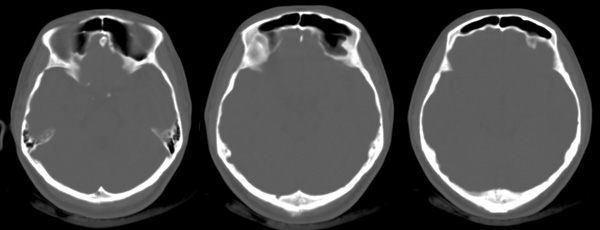

f24y打架后头疼3天,5mm薄扫

ct所见:左侧顶叶近侧脑室体部处示斑片状低密度灶,同侧脑室扩大,脑沟及脑裂增宽。颅骨结构完整。

诊断:符合脑软化灶,可以结合以往病史进行临床分析,如新生儿时的脑缺氧、血管畸形、后天性的各种原因引起的缺血缺氧、陈旧性的外伤等。由于部分容积效应的原因,左侧脑实质的低密度灶看似与侧脑室相通,必要时可以作mr检查以鉴别有无脑穿通畸形的可能。该病灶与此次外伤无关。

左侧侧基底节区软化灶,左侧脑室前角、体部被牵拉扩大,仔细观察左侧侧裂池及部分脑沟增宽,提示左侧颞叶有轻度萎缩,上述改变为陈旧性病变,与此次头外伤无关,其病因分析有以下可能:缺氧、脑炎、外伤等。